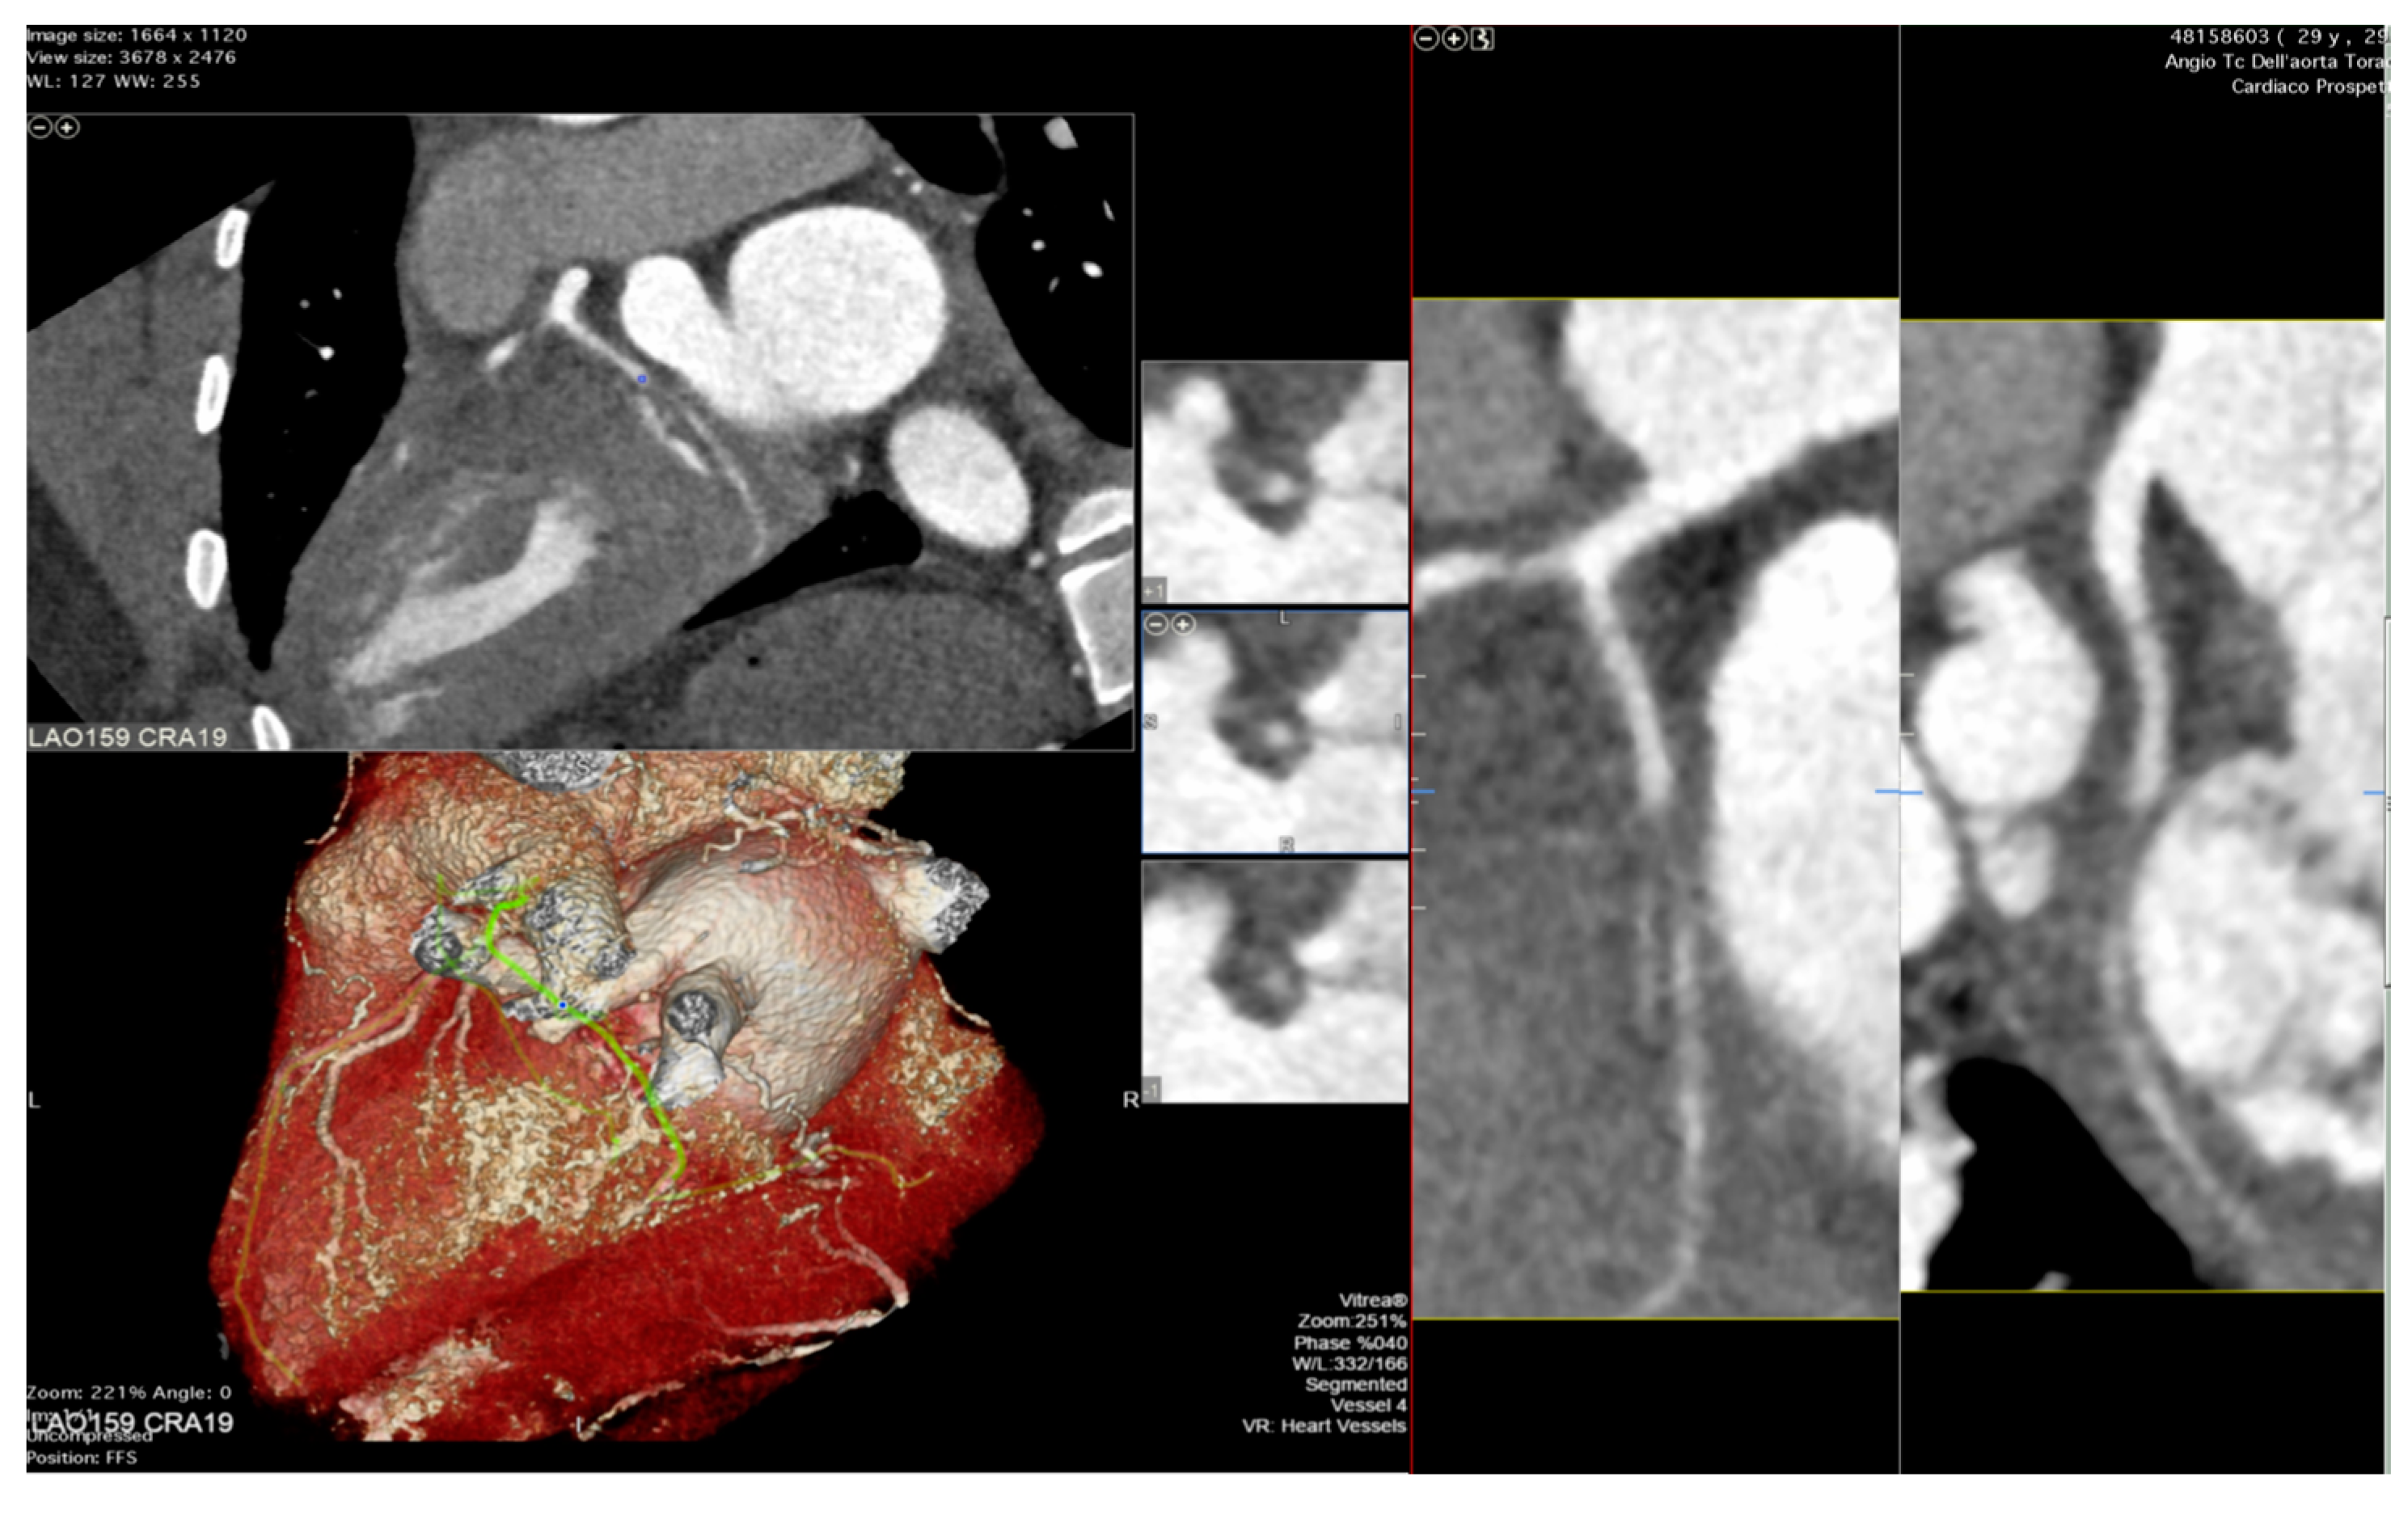

5. Stress Echocardiography

6. The Role of Coronary Computed Tomography Angiography and Nuclear Imaging in the Follow-Up of Heart Transplant Recipients